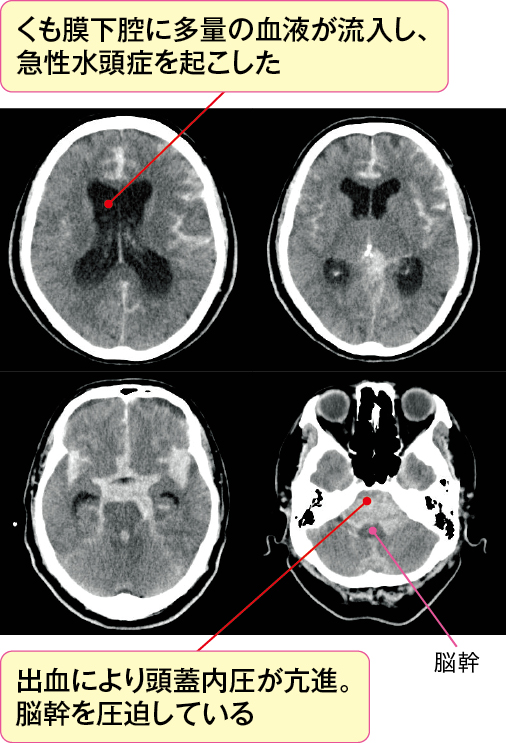

くも膜下出血後の急性水頭症は、出血により急激に脳室やくも膜下腔の容積が増えることで頭蓋内圧が亢進し脳ヘルニア(図4)となり、死につながる危険性があります。

画像上、出血量が多い場合や急性水頭症を起こしている場合には、急性頭蓋内圧亢進症状や表2の症状の出現がないかを観察することが大切です。

表2 脳ヘルニアのサイン

●急激な意識障害

●瞳孔・対光反射異常

●運動麻痺

●異常肢位(除脳硬直・除皮質硬直)

●呼吸障害

●バイタルサインの異常(血圧上昇・除脈)

●噴水様の嘔吐 など

また、くも膜下出血で起こる急性水頭症は、頭蓋内圧を亢進させることで脳血流が低下し、脳血管れん縮を引き起こす要因にもなります(くも膜下出血の画像の見方とケアでの活用ポイント参照)。

急性水頭症による頭蓋内圧亢進を悪化させないために、脳室にドレーンを挿入し、体外に脳室に貯留した髄液・血液を排泄させるドレナージ術などの救命処置を行う場合もあります。